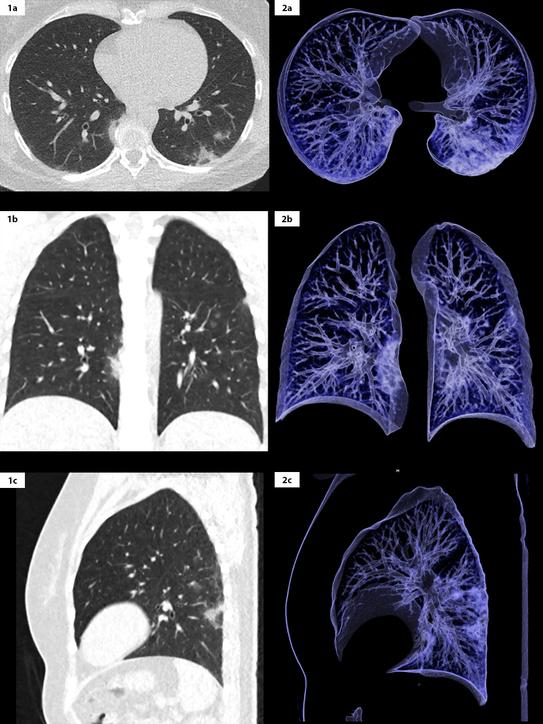

From vidalung.ai

SixMonth Followup Chest CT findings after Severe COVID19 Pneumonia Covid 19 Pneumonia Chest Pain Your doctor might recommend cough medicine and pain relievers that reduce. You may have severe shortness of breath, a cough, a fever, chest pain, chills, or fatigue. In severe cases, myocarditis can lead to heart failure and irregular heart rhythms. It can result from pleuritic pain, muscular pain, angina, or heart damage. Patients must contact their health care. Pneumonia is. Covid 19 Pneumonia Chest Pain.

From pubs.rsna.org